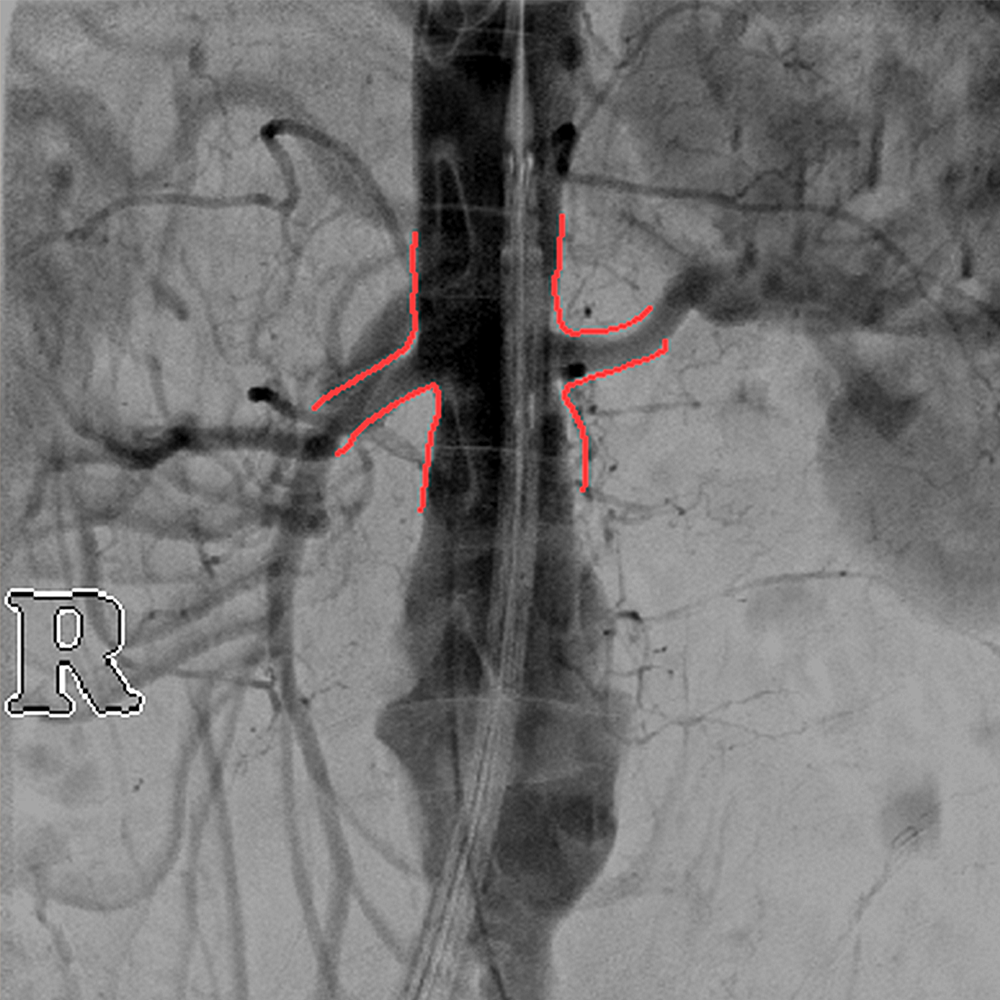

Anatomical Marking Tool (AMT)

Colored markings and annotations on live images

Enhanced Vessel Visualisation (EVV)

Automated vessel detection during vascular interventions

SmartVascular Workflow

A special workflow for complex vascular procedures.